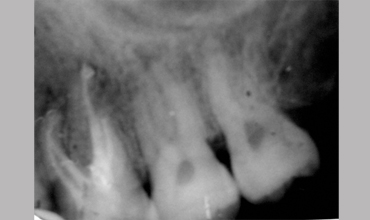

MB2

Management Of Maxillary First Molar With Mb 2 Canal